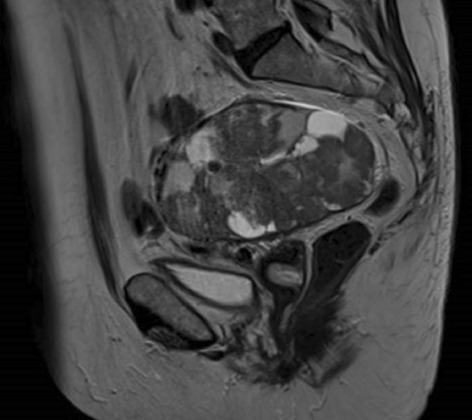

Result: The comparative analysis of the data shows a decrease in the number of presentations in ESU of AC cases during the pandemic, compared to the previous year, most often due to patients' fear of contacting the virus in the hospital environment. The median time between the onset of symptoms and the presentation in the ESU: 2020 – 14 days, 2019 – 5 days. Forms of moderate and severe AC predominated in the pandemic: GradeI—14.28%; GradeII—57.14%; GradeIII—28.57%. In 2019 GradeI—66.39%, GradeII—27.73%, GradeIII—5.88%. Laparoscopic cholecystectomy was attempted for all patients from the beginning, but the complications identified during surgery and severe forms led to a conversion rate in 2020 of 14.28%, compared to 5.88% in 2019. The severity of the cases is also observed in the postoperative complications encountered (perihepatic abscess Fig. 2. Figure 2, wound infection, bile leak; 2019—5.04%, 2020—23.21%), which required surgical reinterventions to solve them (2019: 2.52%, 2020: 10.71%). The number of deaths was significantly higher in 2020 (5.35%), compared to 2019 (0.84%).